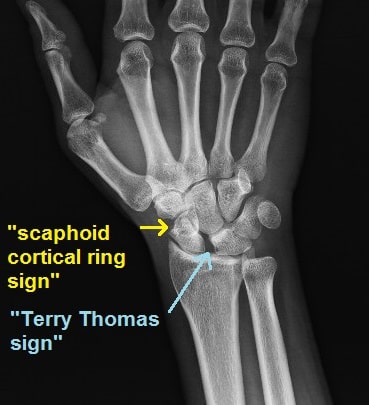

Η διάγνωση για τη ρήξη σκαφομηνοειδούς συνδέσμου βασίζεται σε:

- κλινική εξέταση

- ακτινογραφίες

- μαγνητική τομογραφία

Σε ορισμένες περιπτώσεις, η αρθροσκόπηση καρπού αποτελεί την πιο αξιόπιστη μέθοδο διάγνωσης, καθώς επιτρέπει την άμεση απεικόνιση των συνδέσμων μέσα στην άρθρωση.